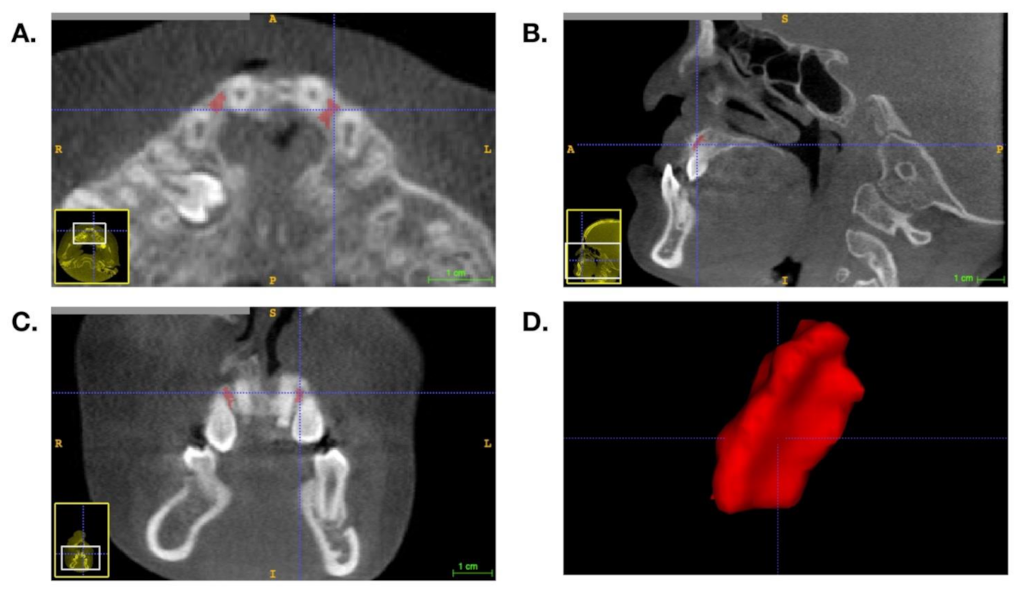

| Definition | Circular zone is located 1 mm from the adjacent teeth. | The largest circular zone that exactly transects the two adjacent teeth or is tangent to the surrounding cortical bone. | A circle is drawn with a diameter of 2 mm. |

| Positive aspect | BMD measurements are not affected by the density of adjacent teeth. |

|

| Negative aspect | The surrounding cortical bone density and air density are often included in examinations of patients with large alveolar gaps. | Easily contains adjacent tooth density or surrounding cortical bone. | Not representative of the overall density in cases with a larger alveolar gap. |

| Operating precautions | — | When measuring, care must be taken of to avoid including sections of the teeth. | Ensure that the distance from the circle to the two adjacent teeth is equal when measuring. |